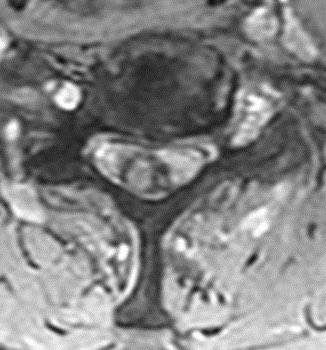

What is the most likely diagnosis in this 65 y/o M presenting w/ leg weakness, hyperreflexia, spasticity and absent vibration sense in the LE? #neu